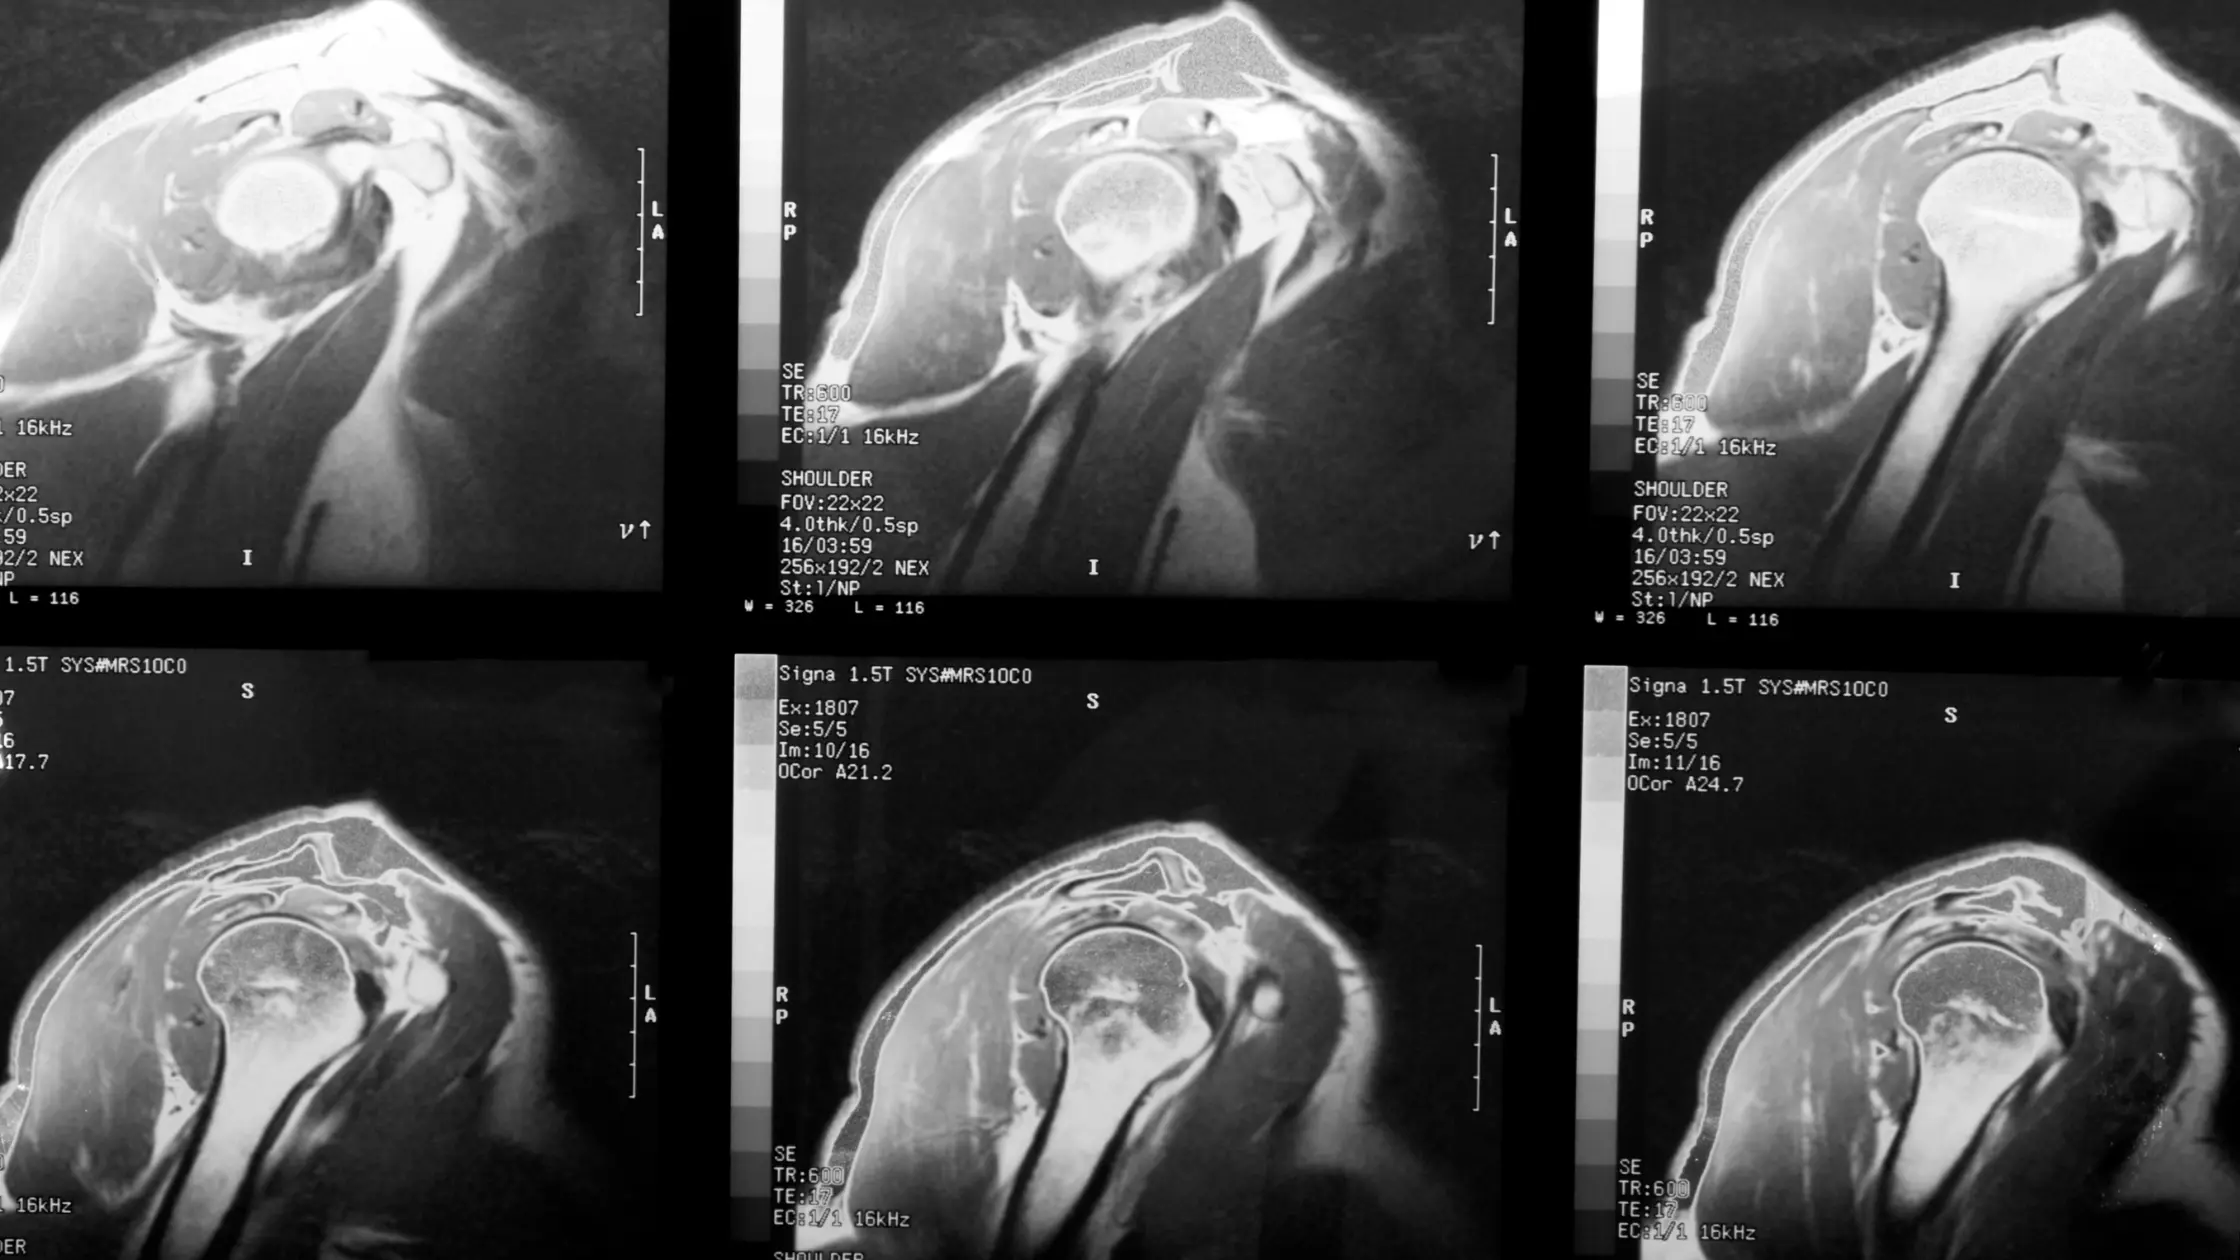

Simptome, cauze și metode de tratament recomandateLeziunea coafei rotatorilor es...